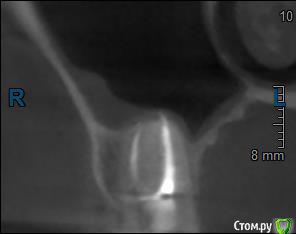

Здравствуйте! Верхний правый шестой зуб пломбировали 3 месяца назад. Примерно месяц назад он начал ныть, после насморка, сначала периодами, а теперь почти постоянно. При постукивание (ощущается не совсем так, как другие зубы) и пальпации десны он не болит. 2,5 месяца назад удаляли кисту из гайморовой пазухи. Может ли быть это какое-то воспаление и есть ли вероятность устранить его какими-нибудь антибиотиками, если да, то как, или может удалить зуб? Если есть воспаление, то какие могут быть последствия если не удалить зуб?

(Снимки с КТ, первые 8(Image) - сделаны сейчас,по 4 в разных проекциях, вторые 8(Before) - сделаны 5 месяцев назад до удаление кисты и повторного пломбирование зуба( до повторного пломбирование он реагировал на горячее, был запломбирован 3 года))

переличили зуб адекватно, во всяком случае по снимкам